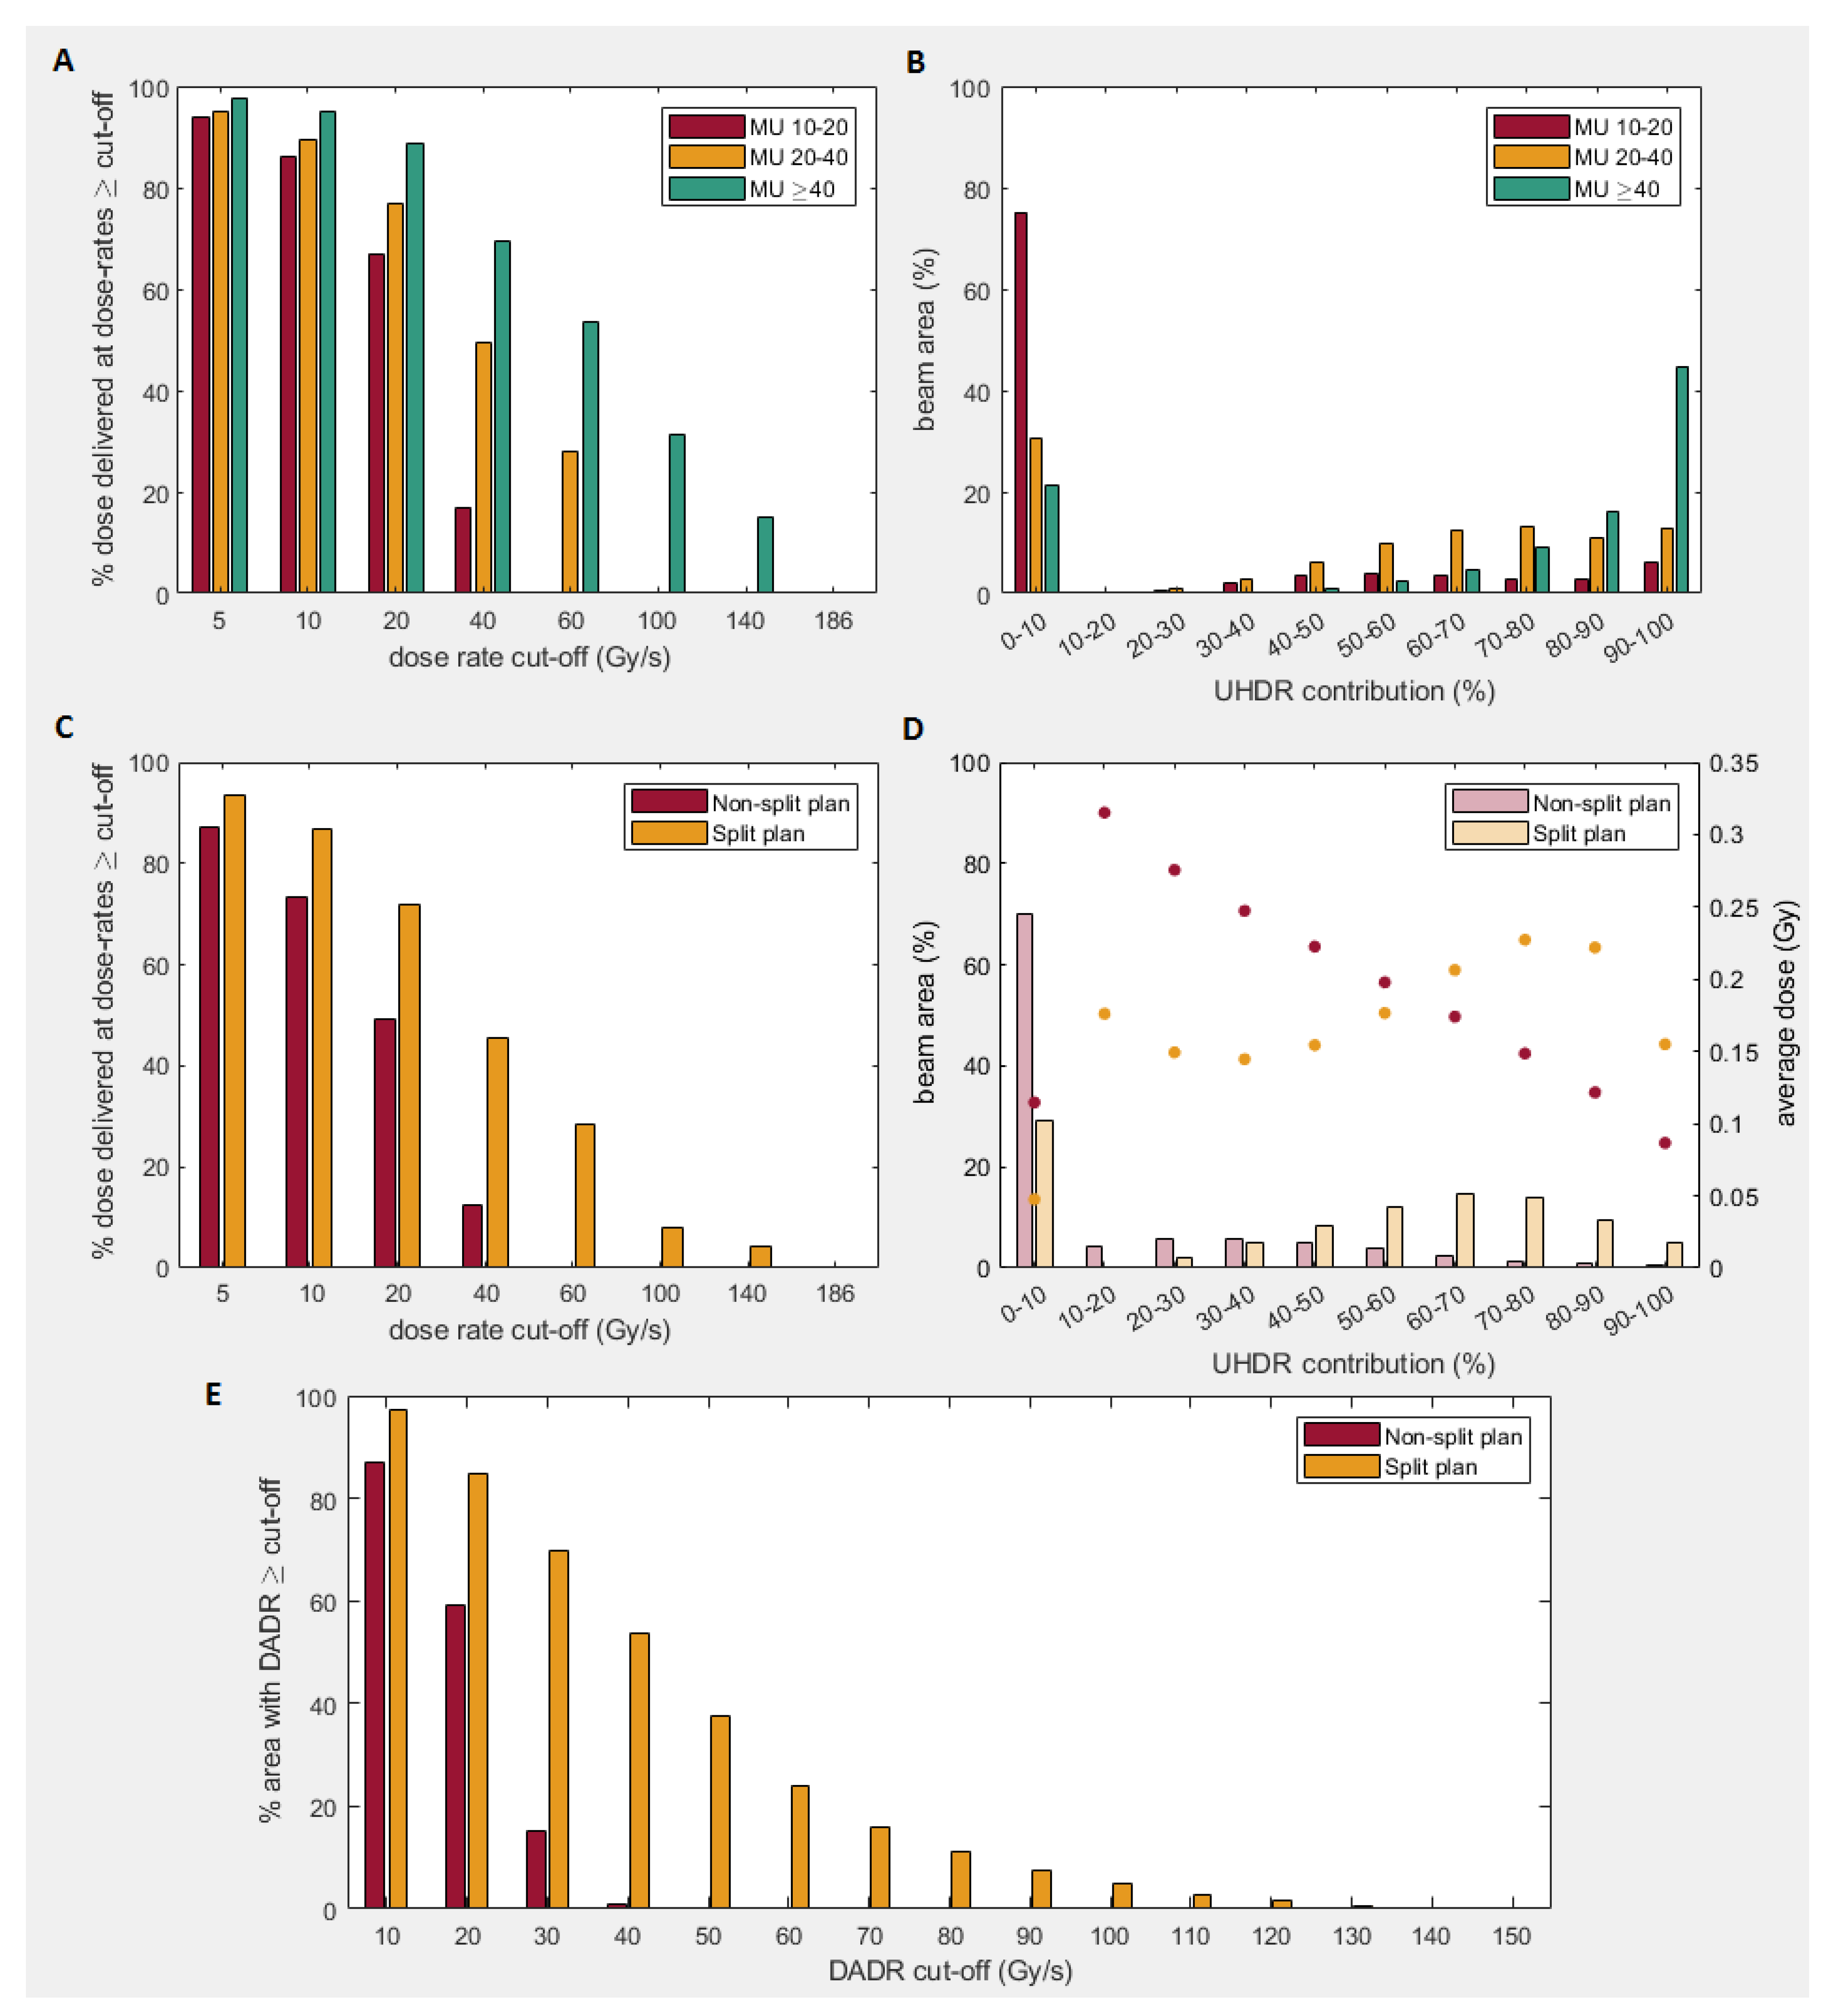

2.2. UHDR Analyses

2.2.1. Dose-Rate

2.3. Plan Splitting

3.2. Dose-Rate

4.2. Dose-Rate